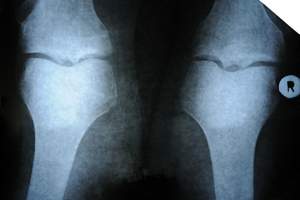

Układ kostno-stawowy